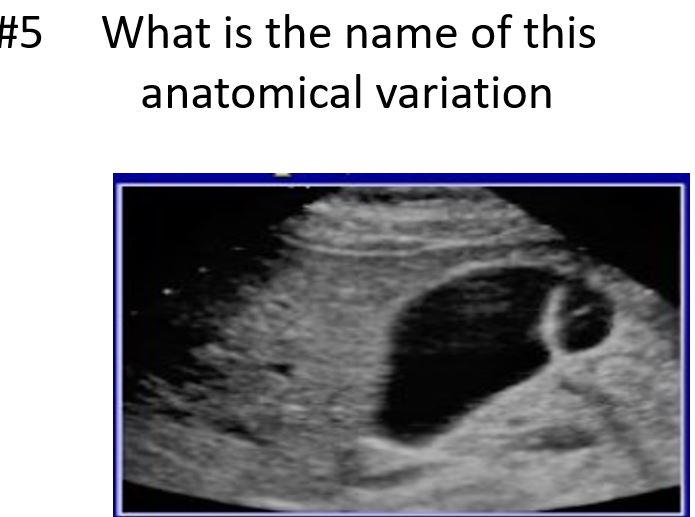

what is another name for this ?

packed bag

phrygian cap

sigmoid gallbladder or junctional folds